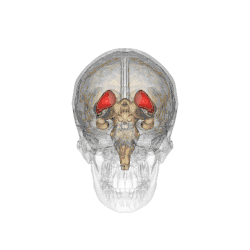

![]() Caudate nucleus (in red) shown within the brain | |

The caudate nuclei are near the center of the brain, sitting astride the thalamus. There is a caudate nucleus in each hemisphere of the brain. Each nucleus is C-shaped, with a wider "head" (caput in Latin) at the front, tapering to a "body" (corpus) and a "tail" (cauda). Sometimes a part of the caudate nucleus is called the "knee" (genu).[6] The caudate head receives its blood supply from the lenticulostriate artery; the tail of the caudate receives its blood supply from the anterior choroidal artery.[7]